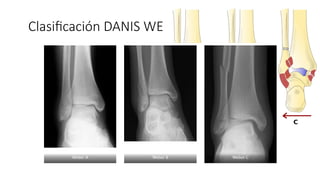

Clasificación DANIS WEBER

• 7.